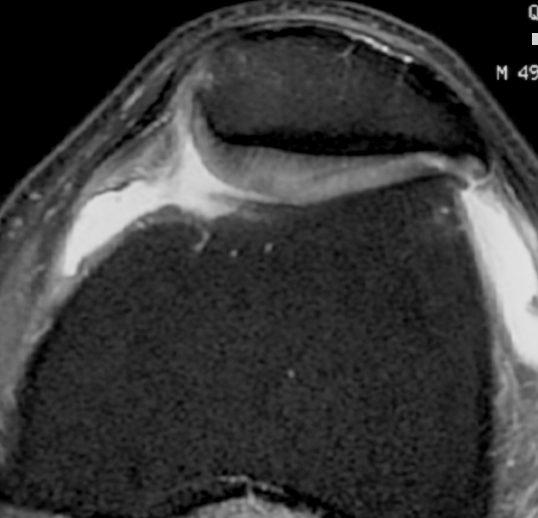

MRI

Moderate lateral facet PJF OA with tilt

Severe lateral PFJ OA in the setting of maltracking / subluxation / tilt